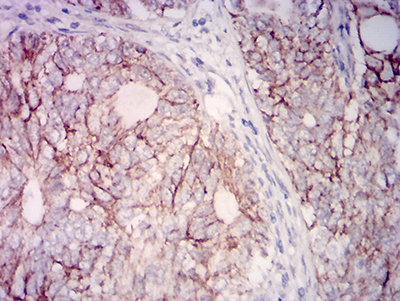

Immunohistochemical analysis of paraffin-embedded cervical cancer tissues using anti-CD315 antibody. The section was pre-treated using heat mediated antigen retrieval with Tris-EDTA buffer (pH 8.0) for 20 minutes. The tissues were blocked in 5% BSA for 30 minutes at room temperature, washed with ddH2O and PBS, and then probed with the primary antibody (EM1712-27, 1/100) for 30 minutes at room temperature. The detection was performed using an HRP conjugated compact polymer system. DAB was used as the chromogen. Tissues were counterstained with hematoxylin and mounted with DPX.